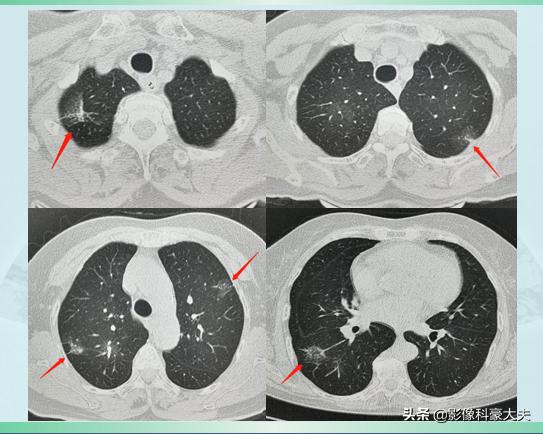

一位70岁的老妇人,头晕恶心5天住院,查房时候跟主治医生说,最近感觉有点胸痛、有点闷,医生于是为她安排了胸部CT检查:

结果很棘手:老人的双侧肺脏,一共发现9个不规则结节灶,最大的3×2cm,几乎都是混合磨玻璃结节,边界清晰,有分叶,有些伴有胸膜牵拉,有些在肺门一侧可以见到供血血管影(右下角箭头所指病灶),这些特点,都符合肺腺癌的影像表现。

老人一共有9个肺癌病灶,都是原发性的,遍布双肺5个肺叶(正常人有5个肺叶,左2右3),难以全部切除了。